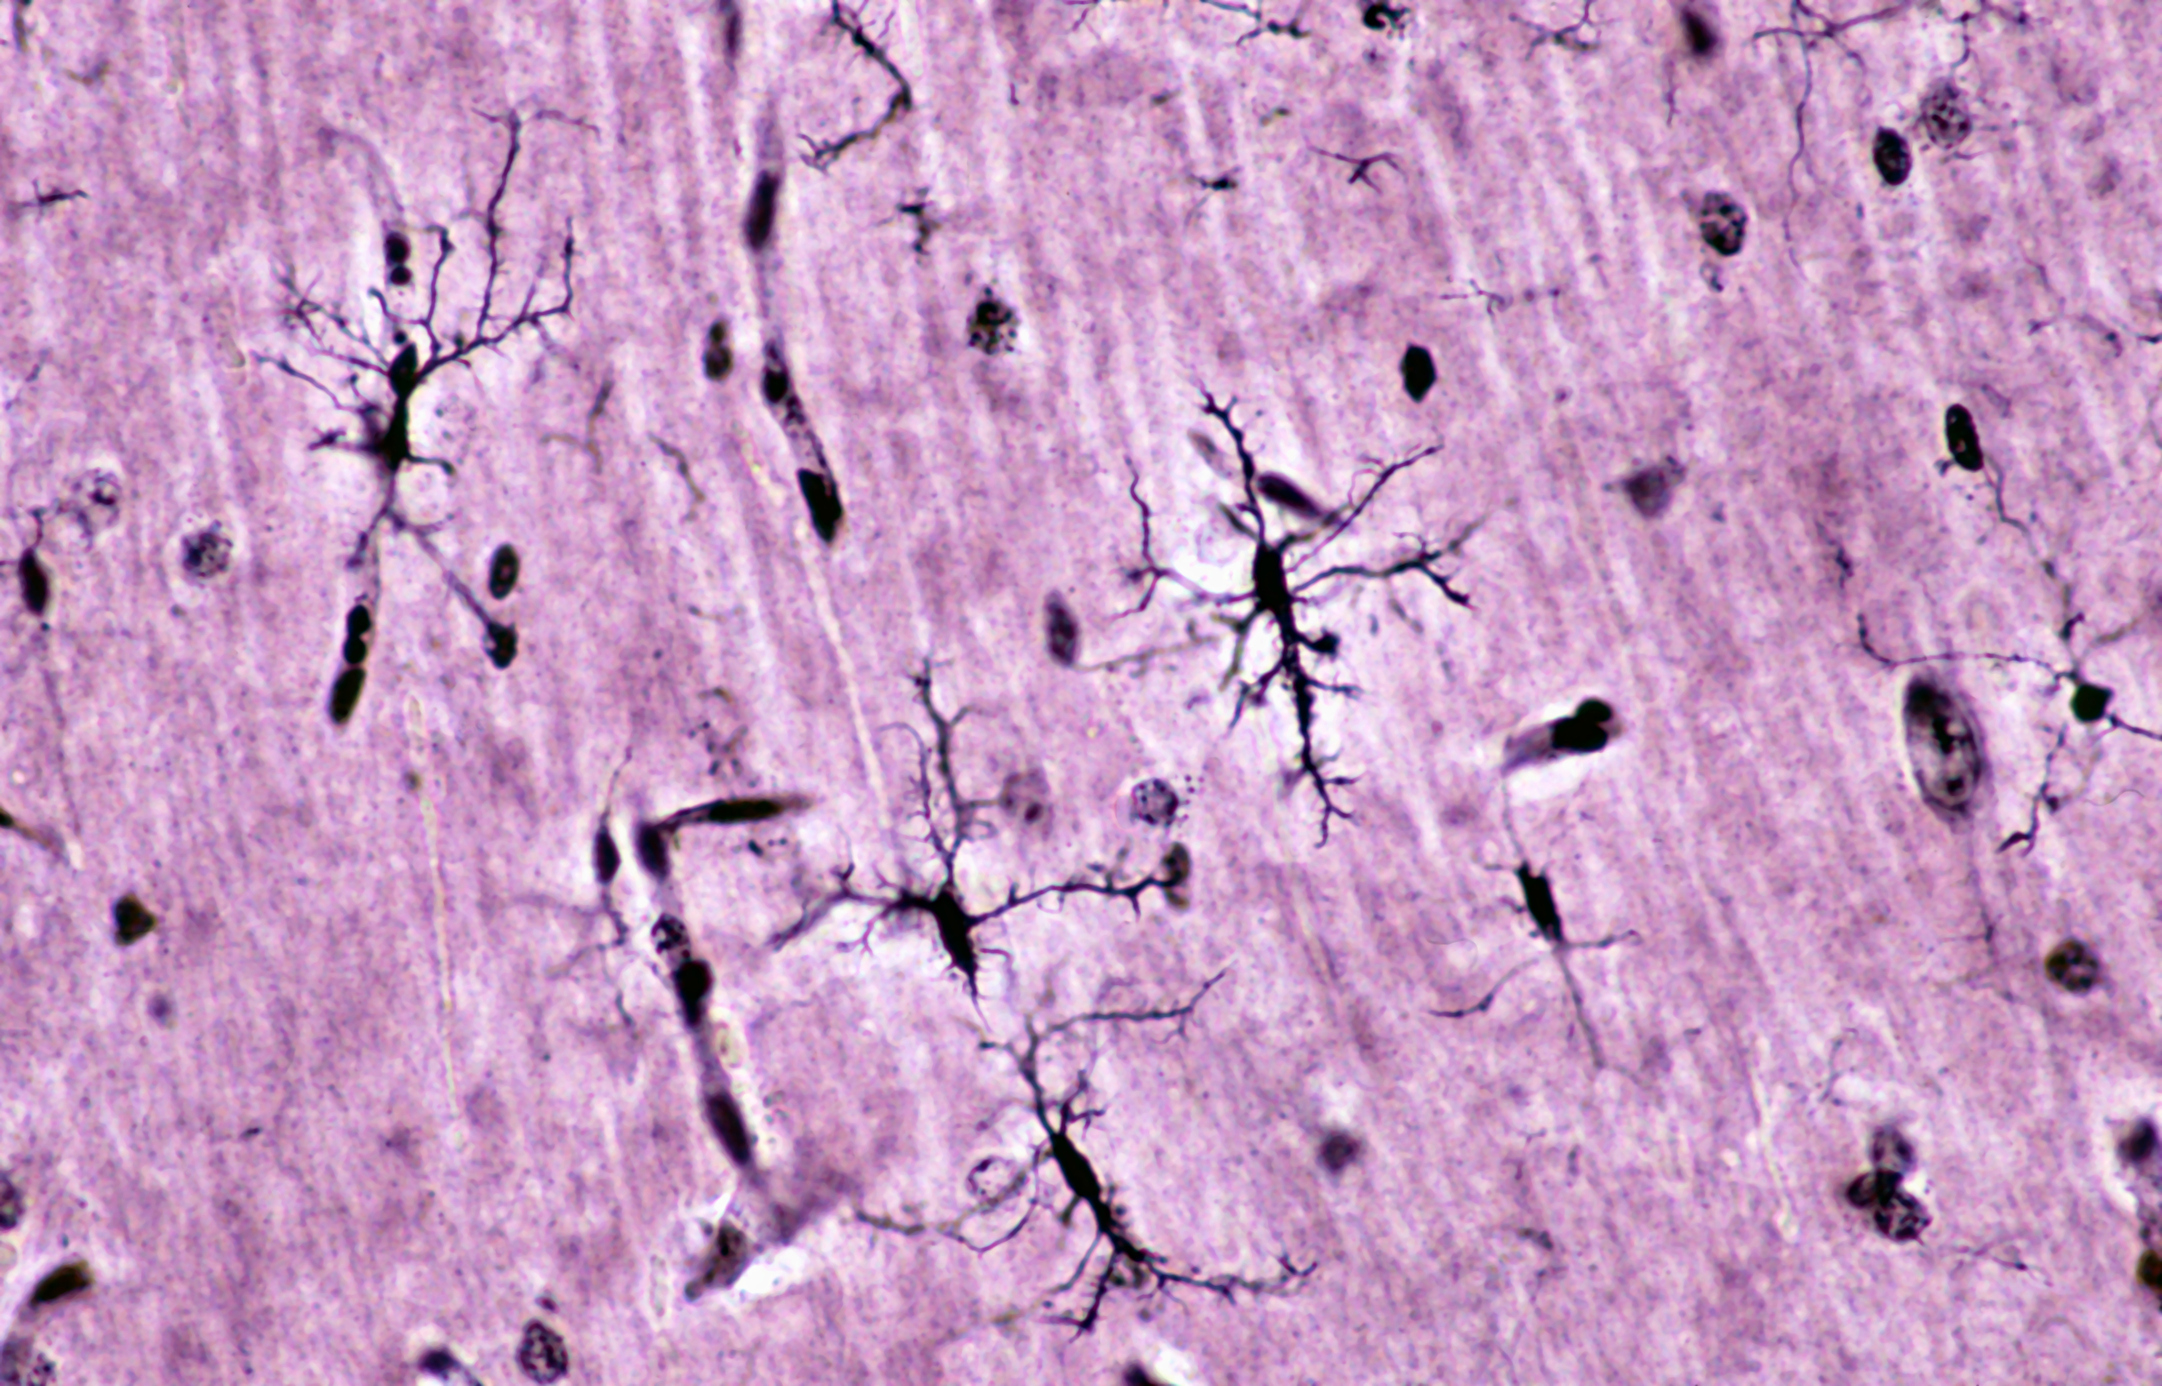

Neuroprotektive Wirkungen des Ginkgo-biloba-Extrakts